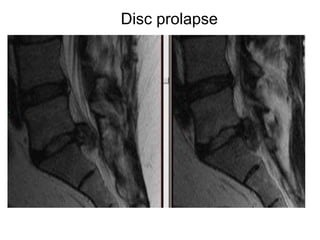

Disc prolapse

Cauda equina syndrome can be caused by anything which compresses the lumbo-sacral nerves  (the cauda equina) Big disc prolapses in young people Tumours which can be primary or metastatic Infection including discitis and spinal abscesses Trauma bone fragments and blood clots Ligamentous hypertrophy in elderly with canal stenosis